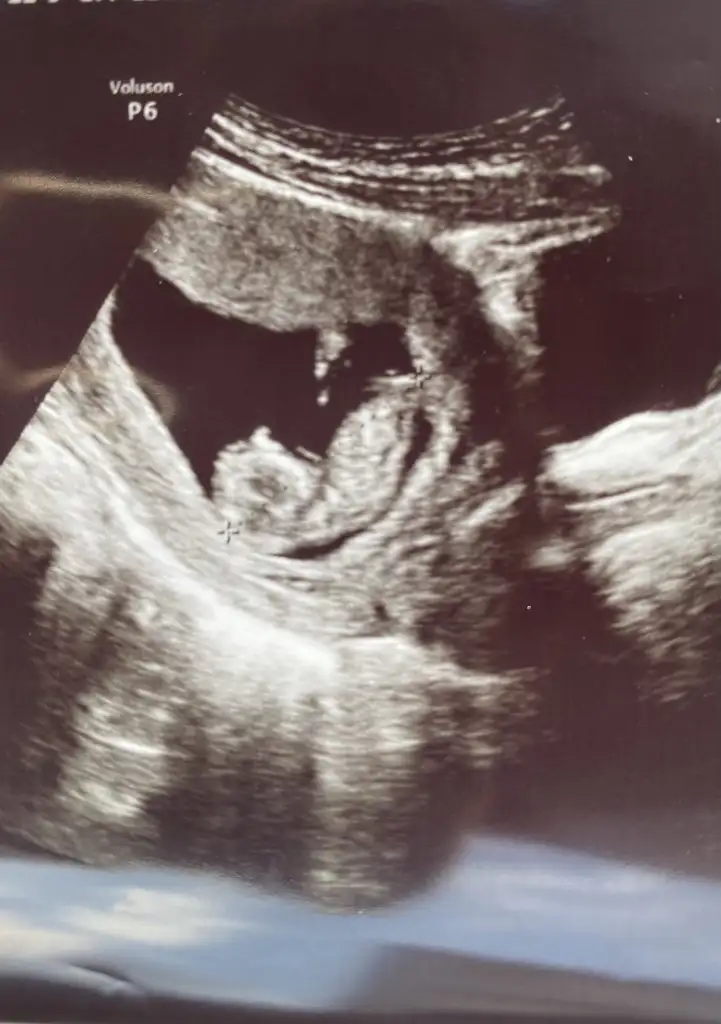

Nubu görünmüyor tipi kız gibi sankiBana da yorum yapabilir misiniz 12 haftada gitmiştim şimdi tekrar gittigimde 18 olucaz ekim sonu merak da var

Çok teşekkür ederimKız gibi

Başka resimlerde var nasıl olması gerekiyor o hafta ikili test filan derken elimde var doktor da kıza benziyor dedi amaNubu görünmüyor tipi kız gibi sanki

Bunlarin dışında da var Bir daha bak buda olmaza diğerlerine bakiyimNubu görünmüyor tipi kız gibi sanki

Kiz görünüyorBunlarin dışında da var Bir daha bak buda olmaza diğerlerine bakiyim

Teşekkür ederim doktora gidince ekim sonu ne derse artık haber veririm..kıza benziyor demişti ilk resim için ikinci resmi doktor görmedi ikili testi yapan doktor gördü..cinsiyet farketmez ama merak işteKiz görünüyor

Erkek gibi sankiKızlar merhaba